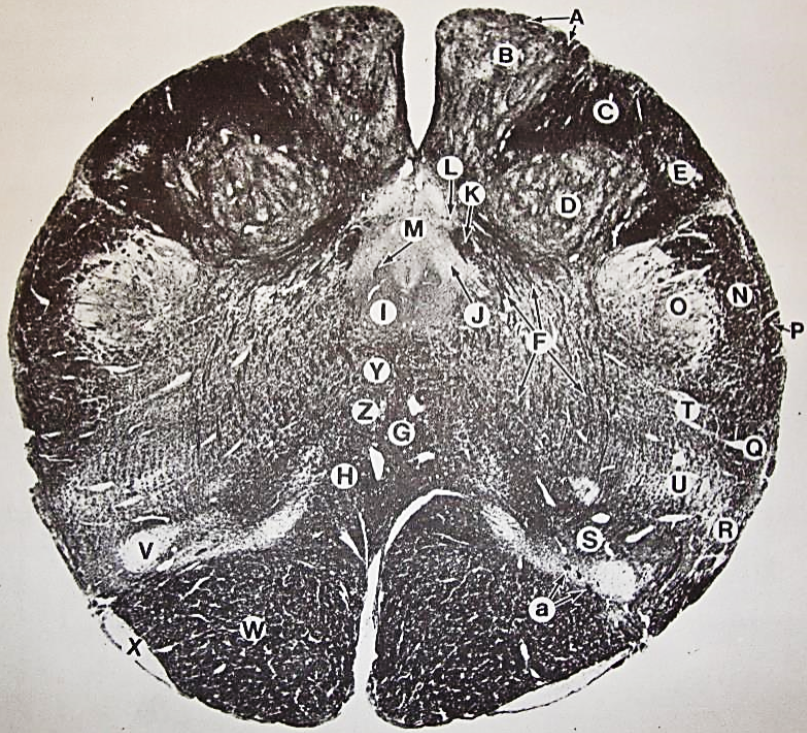

A

posterior median sulcus

B

posterior intermediate sulcus

C

anterior median fissure

D

gracile fasciculus

E

Gracile nucleus

F

fasciculus cuneatus

G

spinal trigeminal tract

H+I collectively

spinal trigeminal nucleus

J

Accessory nucleus

K

pyramidal decussation

L

lateral corticospinal tract

M

rubrospinal tract

N

posterior spinocerebellar tract

O

anterior spinocerebellar tract

P

lateral spinothalamic tract

Q

anterior spinothalamic tract

R

lateral vestibulospinal tract

S

medial longitudinal fasciculus

T

tectospinal tract

U

central canal